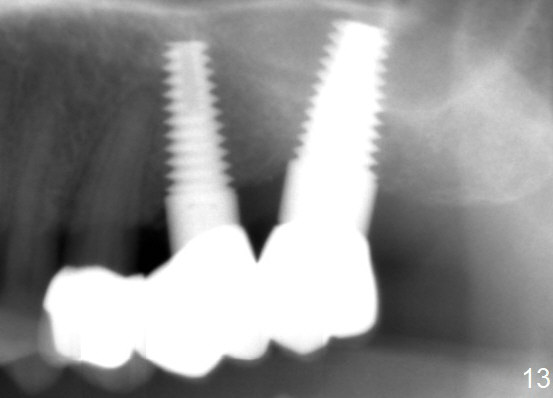

A 58-year-old man used to have a upper left 3-unit bridge. Two months after extraction and immediate implant at the site of the posterior abutment, an implant is planned to be placed at the site of the pontic, #14 (Fig.1). Osteotomy starts with a 1.6 mm pilot drill, followed by bone expanders, parallel to the crown of the tooth #13. The first intraop PA shows that 3.0 mm bone expander is close to the root of the neighboring tooth (Fig.2). No matter what is done to change the trajectory of the osteotomy using expanders according to the crown morphology of the neighboring tooth, the next 3 expander does not improve in parallelism (Fig.3). When a 6x17 mm tap is inserted (Fig.4 T), it is realized that axis of the tap is parallel to the axis of the crown of the neighboring tooth (black line), but not that of the root (red line). It is too late to change the trajectory drastically; a 6x17 mm implant is placed with insertion torque > 60 Ncm (Fig.5). It is best to change the trajectory as early as possible, e.g., after taking the first intraop PA and withdrawing the expander (Fig.6 black area) and as much as possible (red line; starting new osteotomy). It is quite similar to immediate implant. There is no bone loss 2 months postop (Fig.7), 18 months (Fig.8,9) or 34 months (Fig.10)post cementation, in spite of open contact between the crowns (Fig.10 black arrowhead). This is partially due to supragingival margin (Fig.11,12 (immediately pre-cementation)). No bone loss is noted 3 years 5 months post cementation (Fig.13).